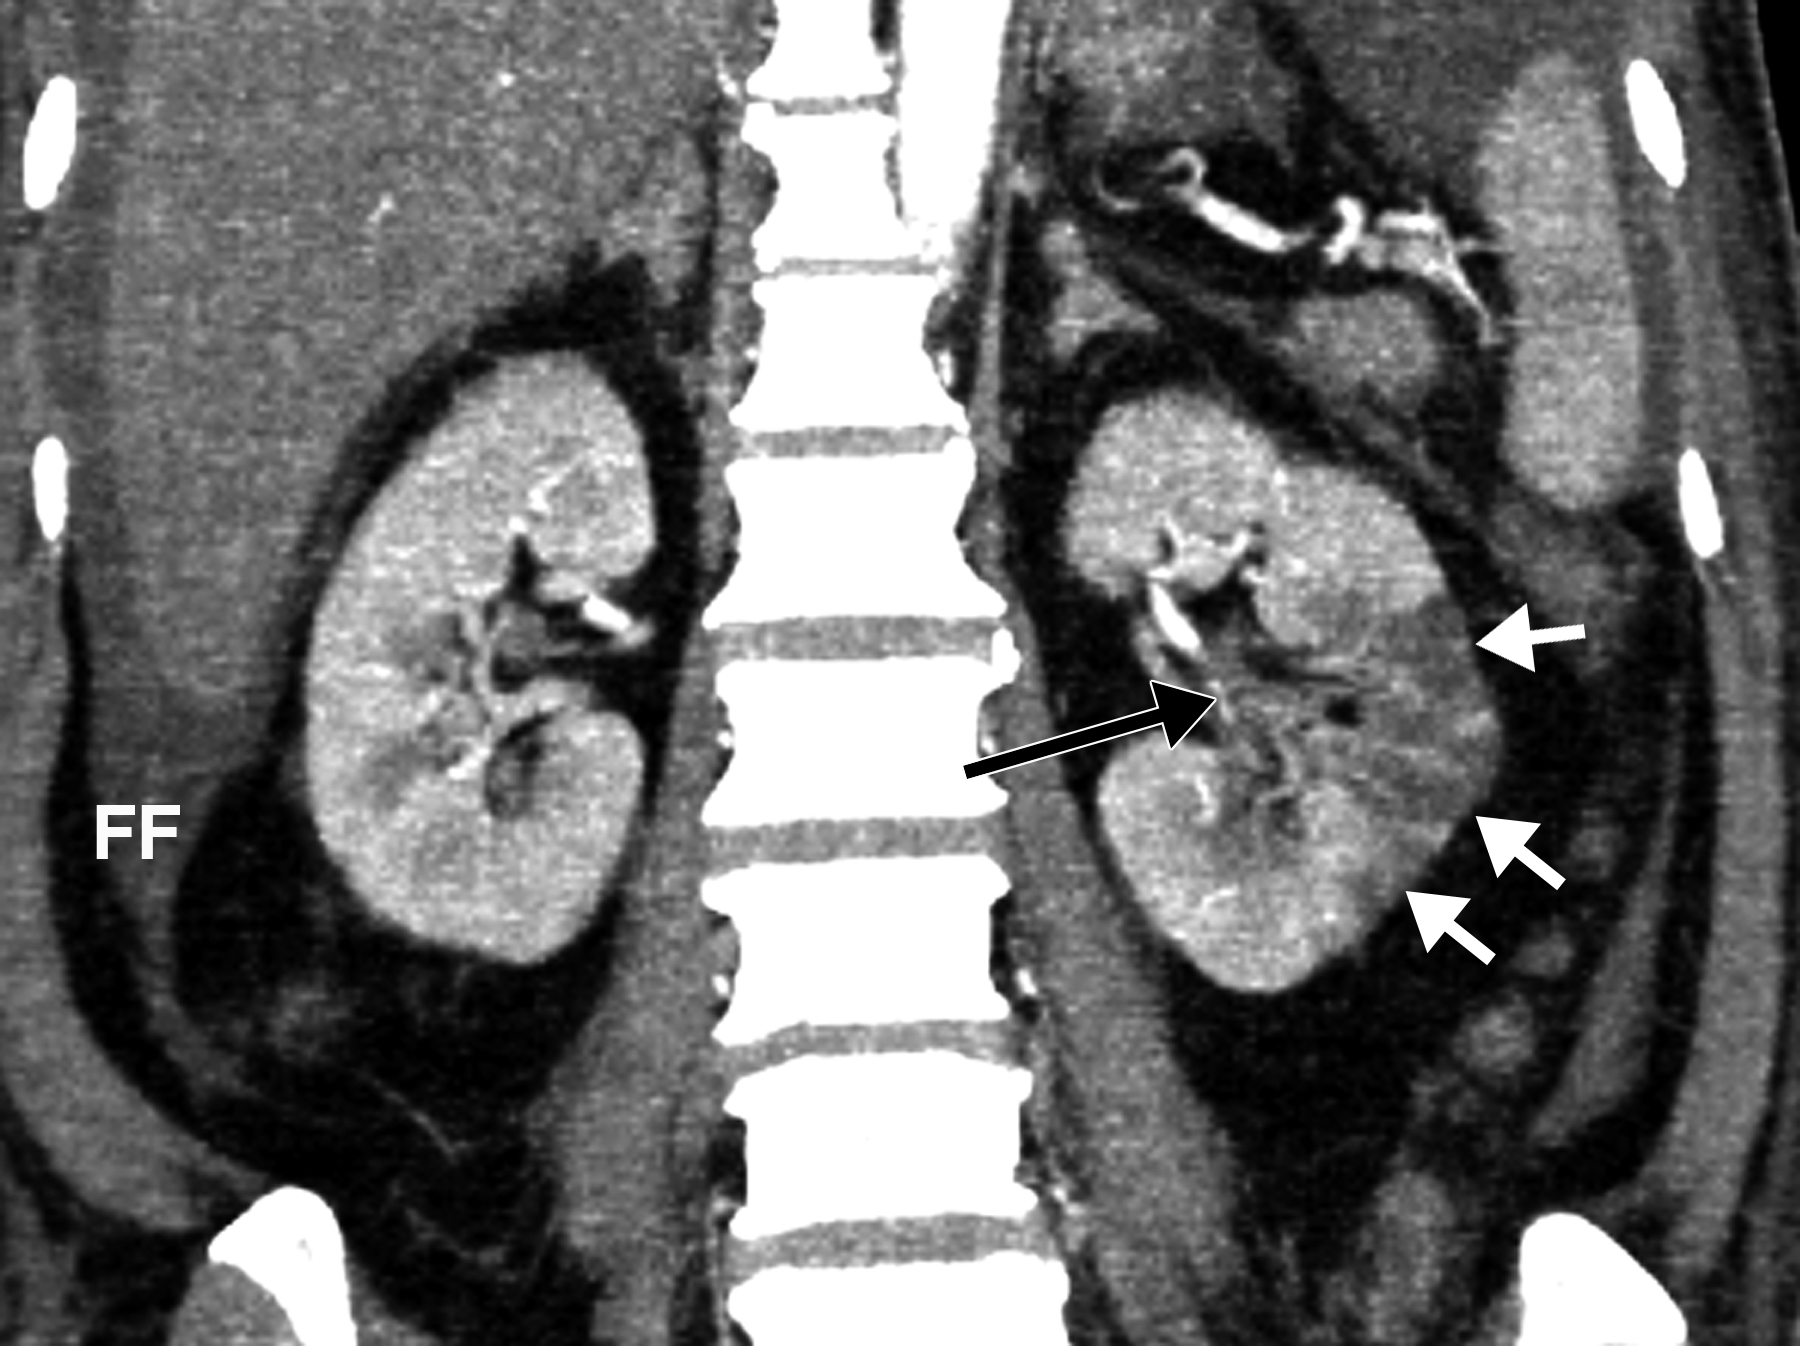

This photo gallery shows the variety of radiological presentations of COVID-19 (SARS-CoV-2) in medical imaging, including computed tomography (CT), radiograph X-rays, ultrasound, echocardiograms and magnetic resonance imaging (MRI). The radiology images show examples of typical COVID pneumonia in the lungs and the numerous complications the virus causes in the body in multiple organs, including the brain, kidneys, heart, abdomen and vascular system.